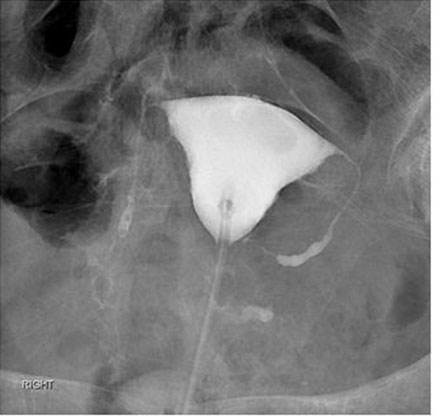

She was managed with oral antibiotics and daily wound dressings. Two weeks later, the second Filshie clip expelled spontaneously in a similar way. Both clips were examined to be closed and complete. She subsequently underwent hysterosalpingography which confirmed non-patency of bilateral fallopian tubes (Figure 2).

Figure 2: Hysterosalpingography using Omnipaque 300 contrast media showing bilateral proximal fallopian tubes opacified with abrupt truncation in their mid to distal segments and normal configuration uterus.